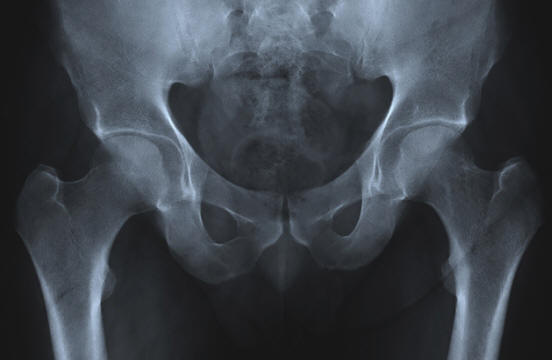

Супер плътни кости

снимка от открити източници

Стареенето неизбежно се свързва с появата на маса физически проблеми. Чест пример е остеопорозата, загубата на кост и плътност. Води до неизбежни фрактури на костите, счупени бедрата и стърчащите гърбици. Група хора обаче притежава уникален ген, в който е скрита тайната на лечението на остеопороза.

Този ген е открит в популация африканери (южноафриканци с Холандски произход). То води до факта, че хората увеличаване на костната маса през целия живот, а не загуби я. По-конкретно, това е мутация в SOST гена, която контролира протеина (склеростин), който регулира растежа на костите.

Ако африканер наследи две копия на мутантния ген, той получава разстройство на склерозата, което води до костна пролиферация тъкан, гигантизъм, пареза на лицето, глухота и ранна смърт. Ясно е че това разстройство е по-лошо от остеопорозата. Но ако Африканер наследява само едно копие на гена, то просто получава плътни кости за цялото живот.

Въпреки че в момента ползите от този ген се използват само неговите хетерозиготни носители учените изучават ДНК на африканерите с надеждата да се намерят начини за обратна остеопороза и други скелетни нарушения. Въз основа на вече получените знания, учените са започнали клинични изпитвания на инхибитор на склеростин, който способен да стимулира образуването на кост.